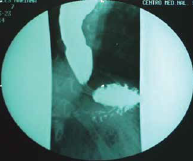

Paciente mujer de 17 años de edad. Antecedentes familiares: hermano que falleció a los 3 años de edad por probable encefalitis viral e hiperpigmentación en mucosas, y padres sin consanguinidad. Antecedentes personales: producto de la segunda gesta, embarazo y partos normoevolutivos, a término, desarrollo psicomotor normal, presentó úlceras corneales a los 18 meses de edad y fue tratada con lubricante y esteroide ocular, sin mejoría clínica. A los 5 años de edad se le diagnosticó alacrimia e hiperpigmentación en zonas de flexión (unión interfalángica proximal, codos, rodillas y tobillos), agenesia bilateral de suprarrenales y renal izquierda por tomografía axial computarizada (TAC); cortisol basal (3.6 µg/dL) y cortisol después de estimulación con hormona adrenocorticotropa (ACTH) (2.1 µg/dL), lo que confirmó el diagnóstico de insuficiencia adrenal, se manejó con terapia sustitutiva esteroidea a 12 mg/m2/SC) por probable diagnóstico de síndrome de Allgrove; 5 meses después presentó crisis convulsiva tipo tónico-clónica generalizada, de 1 minuto de duración, asociada a crisis hipoglucémica, clínicamente con disartria y debilidad muscular (4/5). La TAC de cráneo resultó sin alteraciones anatómicas y, la electromiografía, con neuropatía motora tipo axonal; se manejó con anticonvulsivantes, con mejoría parcial por falta de apego terapéutico, y se incrementó la dosis de esteroide a 15 mg/m2/SC. Un año después, presentó disfagia a sólidos, ganancia ponderal mínima y desnutrición crónica. Se le solicitó una serie esófagogastroduodenal, la cual mostró esófago dilatado en tercio distal y signo en “punta de lápiz” (figura 1). Se procedió a tomar manometría esofágica, que confirmó un aumento de la presión en esfínter esofágico inferior, relajación incompleta, aperístalsis del cuerpo esofágico compatible con acalasia tipo 1 (figura 2); se le realizó cardiomiotomía de Heller y funduplicatura parcial anterior por laparoscopia, y la paciente tuvo mejoría de la sintomatología digestiva.

Figura 1 Serie esofagogastroduodenal con presencia de dilatación en el tercio distal, disminución de la relajación del esfínter esofágico inferior, signo en punta de lápiz, que sí permite el paso de material de contraste hacia estómago.

Los síntomas iniciales se manifiestan en la infancia temprana, el primer síntoma es la presencia de alacrimia, como en esta paciente, que se manifestó desde los 18 meses de edad, con úlceras corneales; otras manifestaciones oftálmicas incluyen queratoconjuntivitis seca, atrofia glandular lacrimal, anormalidades pupilares, ambliopía y atrofia óptica3. La presencia de acalasia se le diagnosticó en la infancia (8 años). Al comparar este dato con la literatura médica internacional, se encontró que la acalasia generalmente se presenta en la vida adulta en un 75% de los casos4, se puede asociar con infecciones virales, degradación neuronal, enfermedades autoinmunitarias, hereditarias o idiopáticas; el diagnóstico se hará con los datos de disfagia y vómito, y en el esofagograma con bario se observará el estrechamiento en la unión esófagogástrica (signo de punta de lápiz)5.